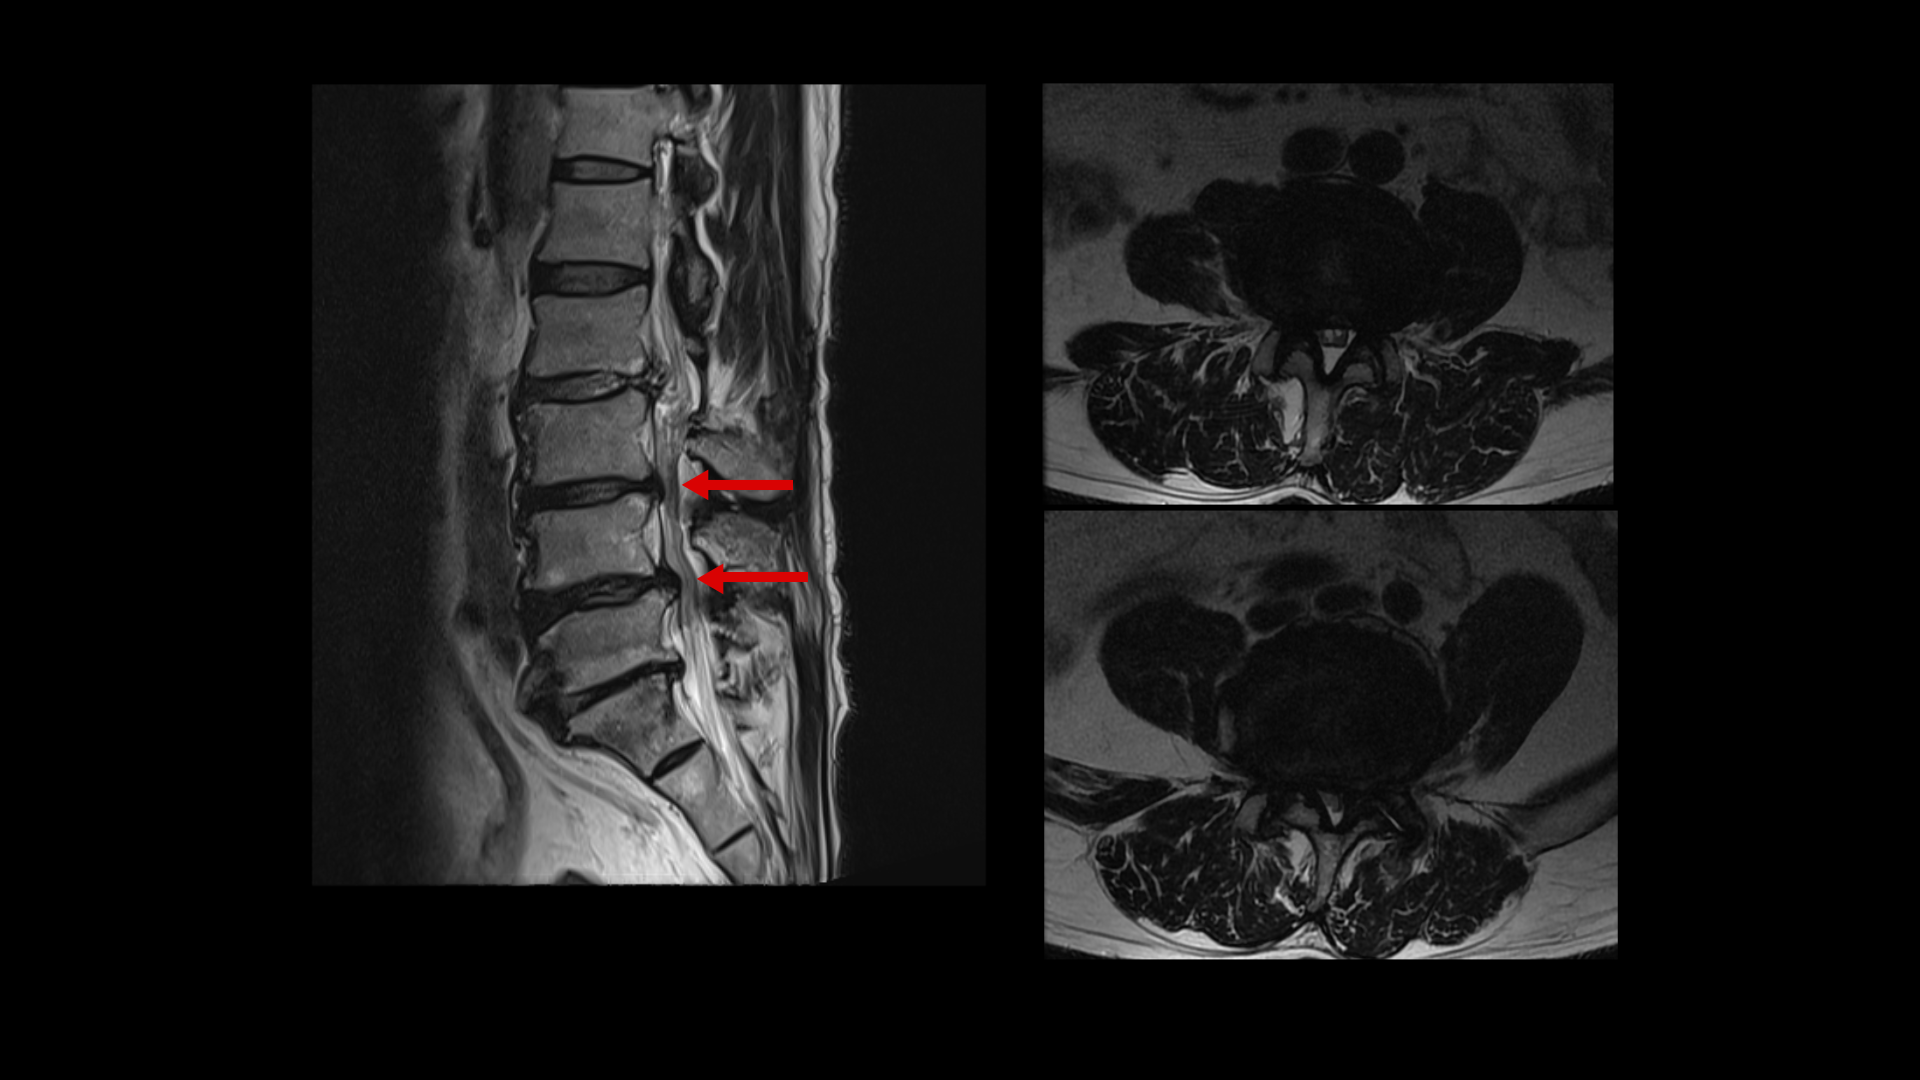

이분 MRI를 보면 네 마디에 퇴행성 디스크가 있고

두 마디에 중심성 협착이 있고

좌우로 나가는 신경구멍이 디스크와 협착으로 많이 좁아져 있습니다.

이를 비교해보면 오른쪽, 왼쪽 다리의 마비 증상과 방사통의 원인인 걸로 추정되는 4번 5번과 5번 1번의 좌우 신경구멍이 비슷한 정도로 막혀 있습니다. 2016년과 2023년의 허리의 신경구멍이 좁아진 정도와 협착 정도는 비슷한 겁니다.